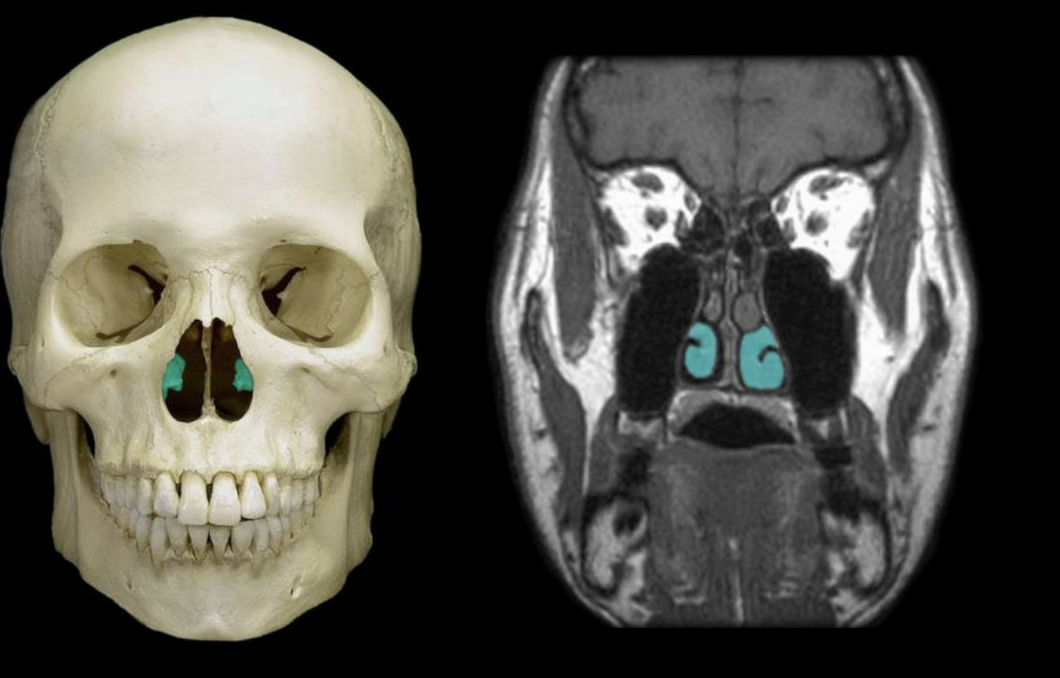

ethmoid bone

knowt flashcard image

nasal conchae

inferior nasal conchae

middle nasal concahe

superior nasal conchae

components of nasal concahe

inferior, middle, superior